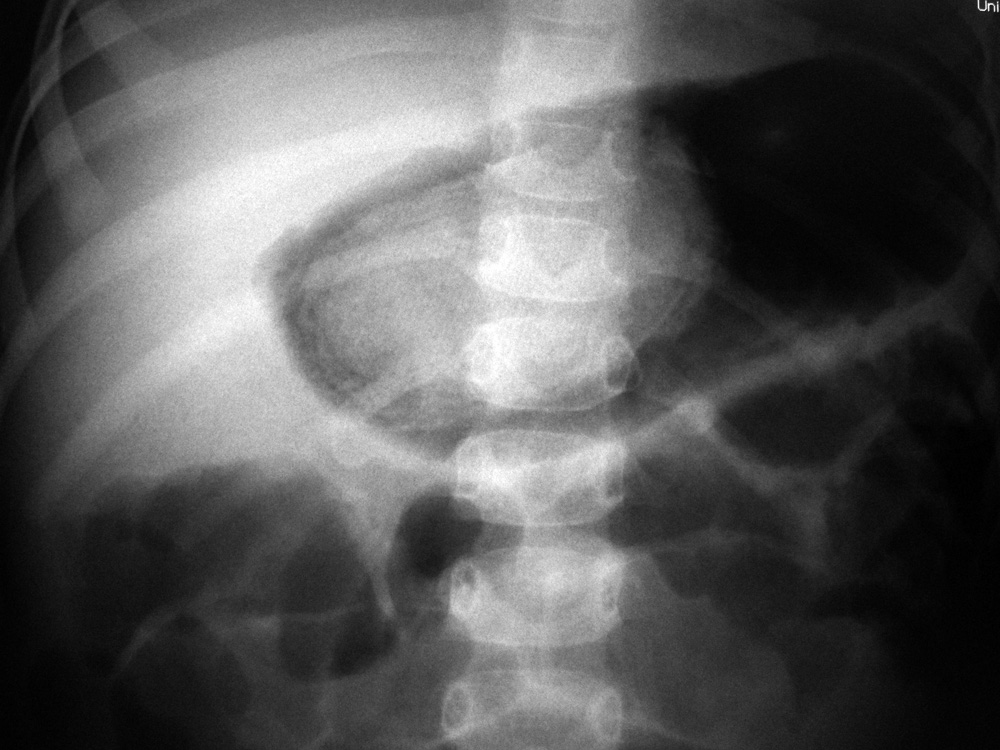

| Sand in the bowel |

| Young child with a history of eating sand. (Courtesy George Barnes, MD). From Hunter, 1994 |